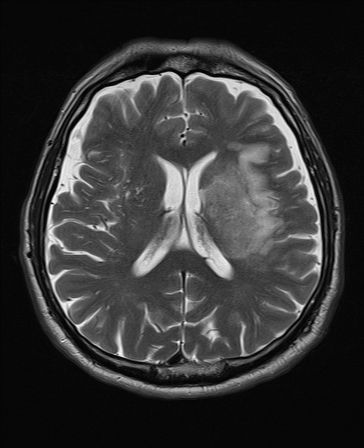

- T2WI: Pathology ๐ฆ; CSF/edema bright. Sensitive to tumours, inflammation, demyelination.

๐ผ๏ธ Example Sequences

| T2 FLAIR | T2 |

|---|---|

| T2-Weighted (T2WI) | CSF, edema, demyelination, most pathology | Fat, calcification, acute haemorrhage | Pathology detection (tumours, inflammation, MS plaques) |